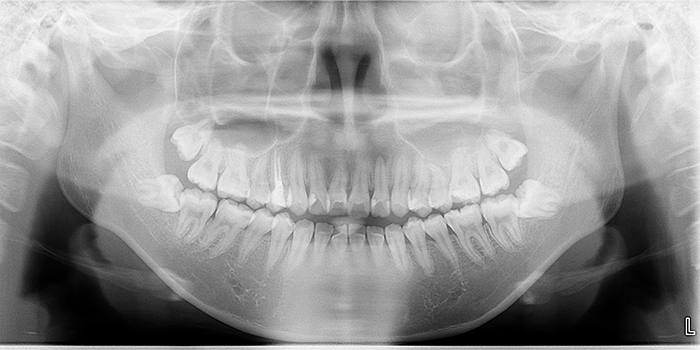

この不安を取り除くため、当院ではお口の中の状態を徹底的に「見える化」しています。

従来のレントゲンに加え、高性能なCTや口腔内カメラを駆使し、患者様ご自身の目で病状や治療プロセスを確認していただきます。

これにより、「分からない」ことから生じる漠然とした不安を解消し、納得感をもって治療を受けていただくことができます。

当院のCTは、2018年の世界販売台数第2位、アメリカでの販売台数第1位の最新型低被ばくCTです。18秒でお口全体のCT撮影が可能で、撮影に必要のX線量は一般的な歯科のレントゲン(パノラマX線写真)の1/5です。